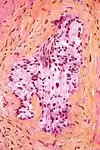

In histology, the HPS stain, or hematoxylin phloxine saffron stain, is a way of marking tissues.

HPS is similar to H&E, the standard bearer in histology. However, it differentiates between the most common connective tissue (collagen) and muscle and cytoplasm by staining the former yellow and the latter two pink,[1] unlike an H&E stain, which stains all three pink.